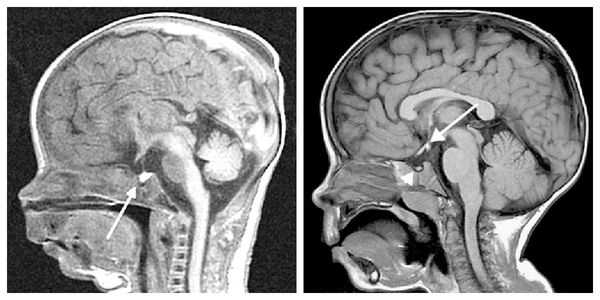

При обнаружении дефицита соматотропного гормона врач может порекомендовать магнитно-резонансную томографию головного мозга и молекулярно-генетическое исследование.

Для выяснения формы нанизма необходимо исследование инсулиноподобного фактора роста (соматомедина-С), ТТГ, ЛГ, ФСГ, Т3, Т4, кортизола в плазме и моче, антител к тиреоглобулину, микросомальной фракции тироцитов и др. Для исключения опухолевого поражения проводится КТ (МРТ) головного мозга.

Для выявления опухолей гипофиза проводится рентгенография черепа, КТ и МРТ головного мозга. При наличии аденомы гипофиза определяется увеличенное турецкое седло (ложе гипофиза). Рентгенограммы кистей рук показывают несоответствие между костным и паспортным возрастом. При офтальмологическом обследовании пациентов с гигантизмом выявляется ограничение зрительных полей, застойные явления в глазном дне.

При необходимости проводится МРТ головного мозга и гипофиза с контрастированием [6] . Она позволяет исключить или подтвердить наличие объёмных образований области гипофиза и головного мозга.